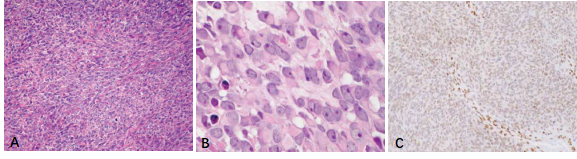

新近研發(fā)的針對SS融合蛋白連接處的特異性抗體SS18-SSX(克隆號E9X9V,圖1,引自參考文獻3)在滑膜肉瘤腫瘤細胞核呈中等至強陽(yáng)性表達(圖2),其靈敏度和特異度分別達95%和100%[3, 4]。研究表明[5],SS18-SSX IHC在診斷SS方面和FISH等分子檢測方法具有很好的一致性(圖3,引自參考文獻5),甚至比其他方法檢測SS更有特異性,特別是在非典型FISH模式的病例中(圖4,引自參考文獻5),它與RNA測序結果有很好的相關(guān)性,有充分的證據說(shuō)明此抗體在診斷SS方面已經(jīng)替代了FISH檢測方法。

圖2.雙相型滑膜肉瘤(A.HE染色,中倍放大)。免疫組化染色SS18-SSX(E9X9V)腫瘤細胞核彌漫強陽(yáng)性(B.低倍放大,C.高倍放大)